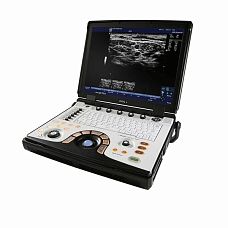

Philips Sparq ультразвуковой аппарат

Характеристики Philips Sparq ультразвуковой аппарат

- LCD монитор диагональю 17 дюймов

- 3 порта для датчиков

- 5 съёмных запоминающих устройств USB на системе

- встроенный дисковод DVD RW

- Кнопка iScan для автоматической опмизации в режимах 2D/Допплер/ЦДК

- Кнопка AutoScan для плавной автоматической оптимизации

- Клавиши быстрого доступа

- Кнопка для выбора датчика и тканеспецифичной визуализации

- Режим ожидания (Sleep Mode) позволяет пользователю сохранить заряд аккумуляторной батареи, если система не используется

Philips Sparq уникальный УЗ аппарат с полностью планшетным интерфейсом управления, помещенным в аппарат стационарного типа. Philips Sparq хорошо подойдёт для быстрого обследования пациента. В системе есть специальный «простой» режим, в котором подсвечиваются только самые необходимые функции.

Высокая производительность УЗИ аппарата Philips Sparq в сочетании с интуитивным интерфейсом Intuitive Dynamic Interface, помогает специалисту в короткие сроки провести исследования с превосходным уровнем детализации изображения.